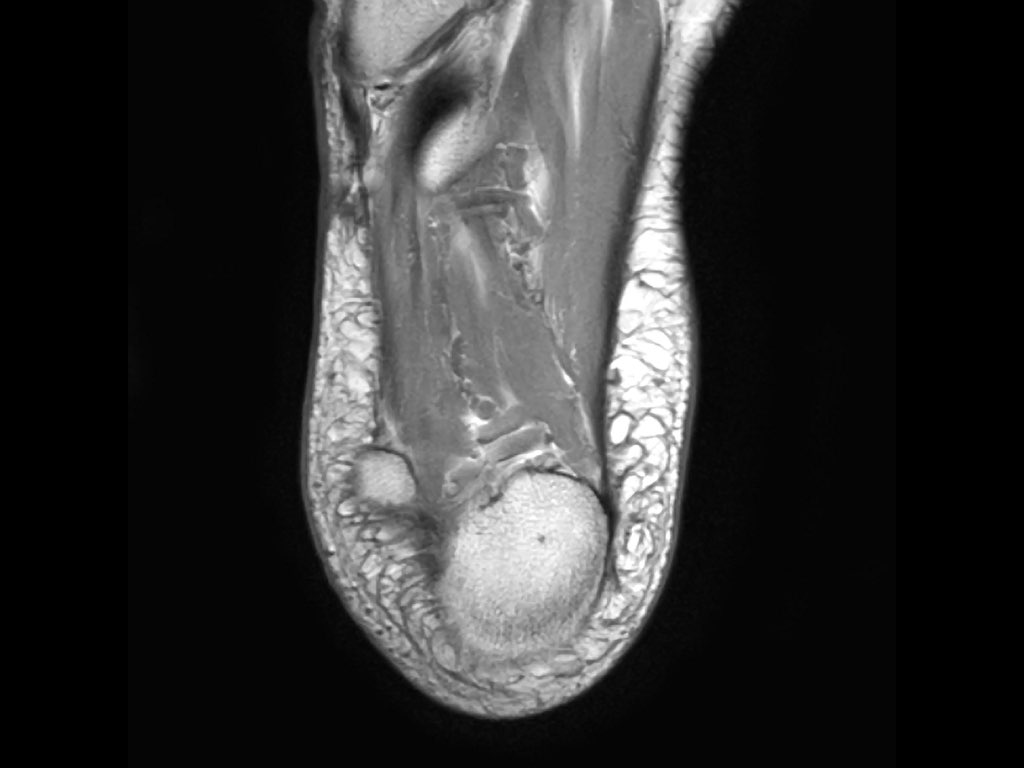

- Khoang ngoài

- Gân cơ mác dài (Peroneus Longus)

- Gân cơ mác ngắn (Peroneus Brevis)